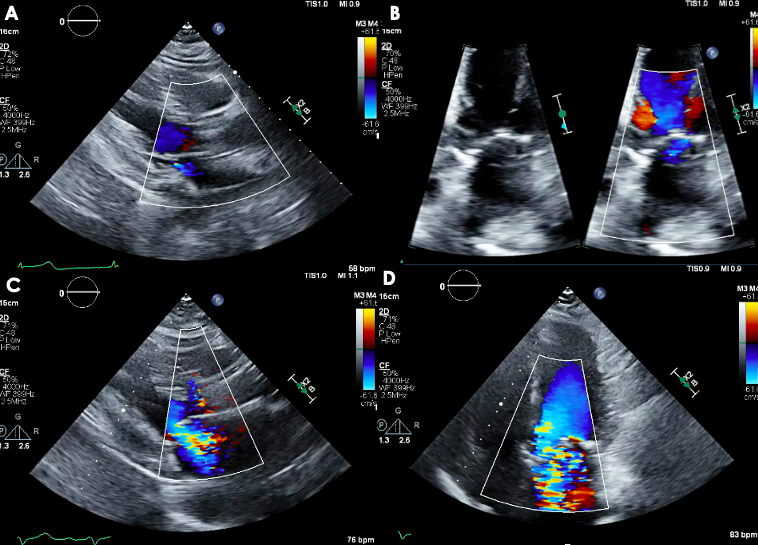

📝 Want to know contemporary & future options for the management of severe 2ndary MR? Check out this new JCF SotA Review to learn about TEER & emerging transcatheter MV repair & replacement devices here! 🔗bit.ly/4fbGuKY